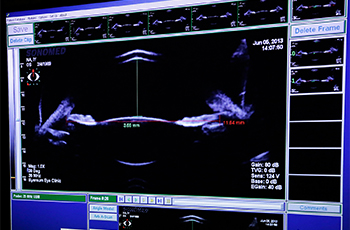

A-Scan 검사

초음파를 이용하여 눈 속의 상태를 검사하는 것입니다. 이를 통해 백내장 수술이나 안내렌즈삽입술에 필요한 안축정 길이, 전방 깊이, 눈 속에 이물질, 망막의 상태 확인 등의 검사를 하게 됩니다.